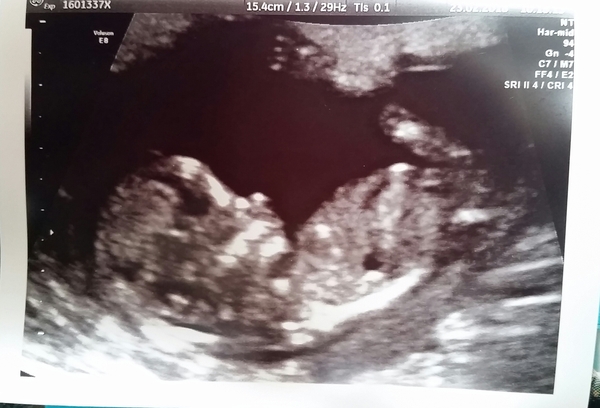

louella99 · 23/02/2018 13:54

Hello! Have been lurking for a while as wasn't sure of due date etc but had my scan today at 13+1 and have been given a due date of August 30th. Seems a few on this thread have that date!

Here's my scan pic. Backwards-lying uterus so hard to scan at this stage apparently. Full bladder was just hiding the uterus. Emptied my bladder as per instruction and it was even worse! Managed to get this one good picture though Smile

Thats a lovely scan pic @louella99